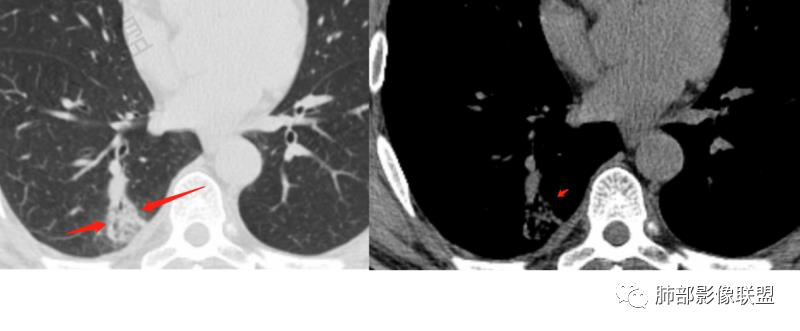

第一次CT:右肺下叶实性结节,近段血管束增粗并与结节相连,结节边缘光滑,密度均匀。第二次(间隔九天,治疗后复查):结节增大,伴有磨玻璃,边界欠清,远端树丫,结节内可见空泡影,壁光滑,临床无明显症状,短期增大先考虑非肿瘤性病变,炎性假瘤,结核,隐球菌。

中年男性患者,1年前发现肺结节,7天前复查结节较前增大,有糖尿病且控制不佳,胸部CT:右肺下叶后段类圆形结节病灶,边界清楚,内部密度均匀,治疗后见内壁光滑的小空洞,结节远端有阻塞性炎症,考虑炎性病变,结核可能,鉴别鳞癌。

右肺结节,气管堵塞,结节边缘光滑,密度均匀,远端斑片影。治疗后复查结节增大,空洞,斑片影伴有磨玻璃,边界欠清,糖尿病,短期增大,考虑结核,隐球菌。

男性病人48岁,既往有糖尿病的病史,影像学表现,右肺下叶后段类圆形的小结节病灶 ,边界比较光整,内见小空洞影 ,病灶远端见小片状的渗出性病灶,增强扫描病灶轻度的强化。病灶在治疗的过程中短期内有增大。整体病灶表现为一个光整结节+远端阻塞性肺炎+小空洞+轻强化,周围无卫星病灶,考虑感染性病变,隐球菌感染?结核次考虑。

右肺下叶结节,边缘光整,密度均匀,伴阻塞炎症,增强无强化,抗感染一周复查效果差,结节内小空洞,阻塞明显,胸膜增厚,糖尿病病史,首先考虑结核,隐球菌待排

糖尿病病史,右肺下叶结节,边缘光整,密度欠均匀,远端阻塞炎症,增强强化不明显,抗感染一周复查,结节较前增大,内出现小空洞,阻塞明显,胸膜增厚,首先考虑结核,隐球菌待排。

中年男性,糖尿病史,无症状。右肺下叶类圆形结节,边缘光滑,支气管近端阻塞,远端淡片影,树芽还是阻塞性炎症?感觉像树芽,沿支气管分布,无明显强化,治疗一周后复查CT,支气管通而不畅,近端小空洞,远端淡片影加重。考虑肺结核可能性大,鉴别肺癌并阻塞性肺炎。

中年男性,糖尿病史,无症状。右肺下叶类圆形结节,边缘光滑,远端树芽征,沿支气管分布,无明显强化,治疗一周后复查CT,支气管通而不畅,近端小空洞,远端树芽征进展为磨玻璃影。考虑肺结核可能性大。

中年男性患者,有糖尿病基础。右下肺结节较1年前增大,CT表现:右肺下叶后段类圆形结节,边界清楚,边缘部分膀隆、部分平直,内部大部分密度均匀,其中见小条状低密度影(粘液栓?),近端支气管堵塞(抗感染治疗后见大部分通畅,近端支气管进入截断入口圆钝、远端支气管稍扩张),综合考虑结核可能性大,治疗后病灶呈支气管挂果,注意鉴别错构瘤。